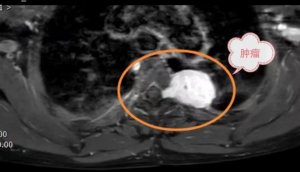

【一院技术】多学科联合攻坚 济宁市第一人民医院成功实施复杂后纵隔肿瘤切除术

近日,济宁市第一人民医院胸外科与神经外科通力协作,成功为一名...